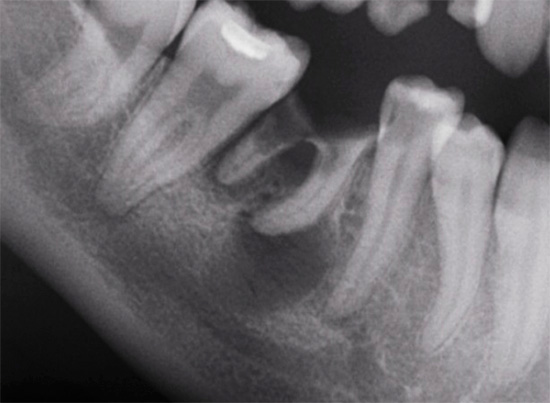

No contexto da exacerbação da periodontite, a situação com o dente é realmente deprimente:

- na cavidade cariosa, há tecidos cariados amolecidos e pigmentados;

- dentro dos canais radiculares, uma polpa inflamada ("nervo") se rompe (na verdade apodrece);

- ao redor da parte superior das raízes do dente, há graus variados de rarefação pronunciada do tecido ósseo - na imagem, ele aparece como manchas escuras, linhas, dentes, etc.

Em tal situação, existe um alto risco de deixar o processo infeccioso no buraco, mesmo depois que todas as raízes com cistos são extraídas dele.